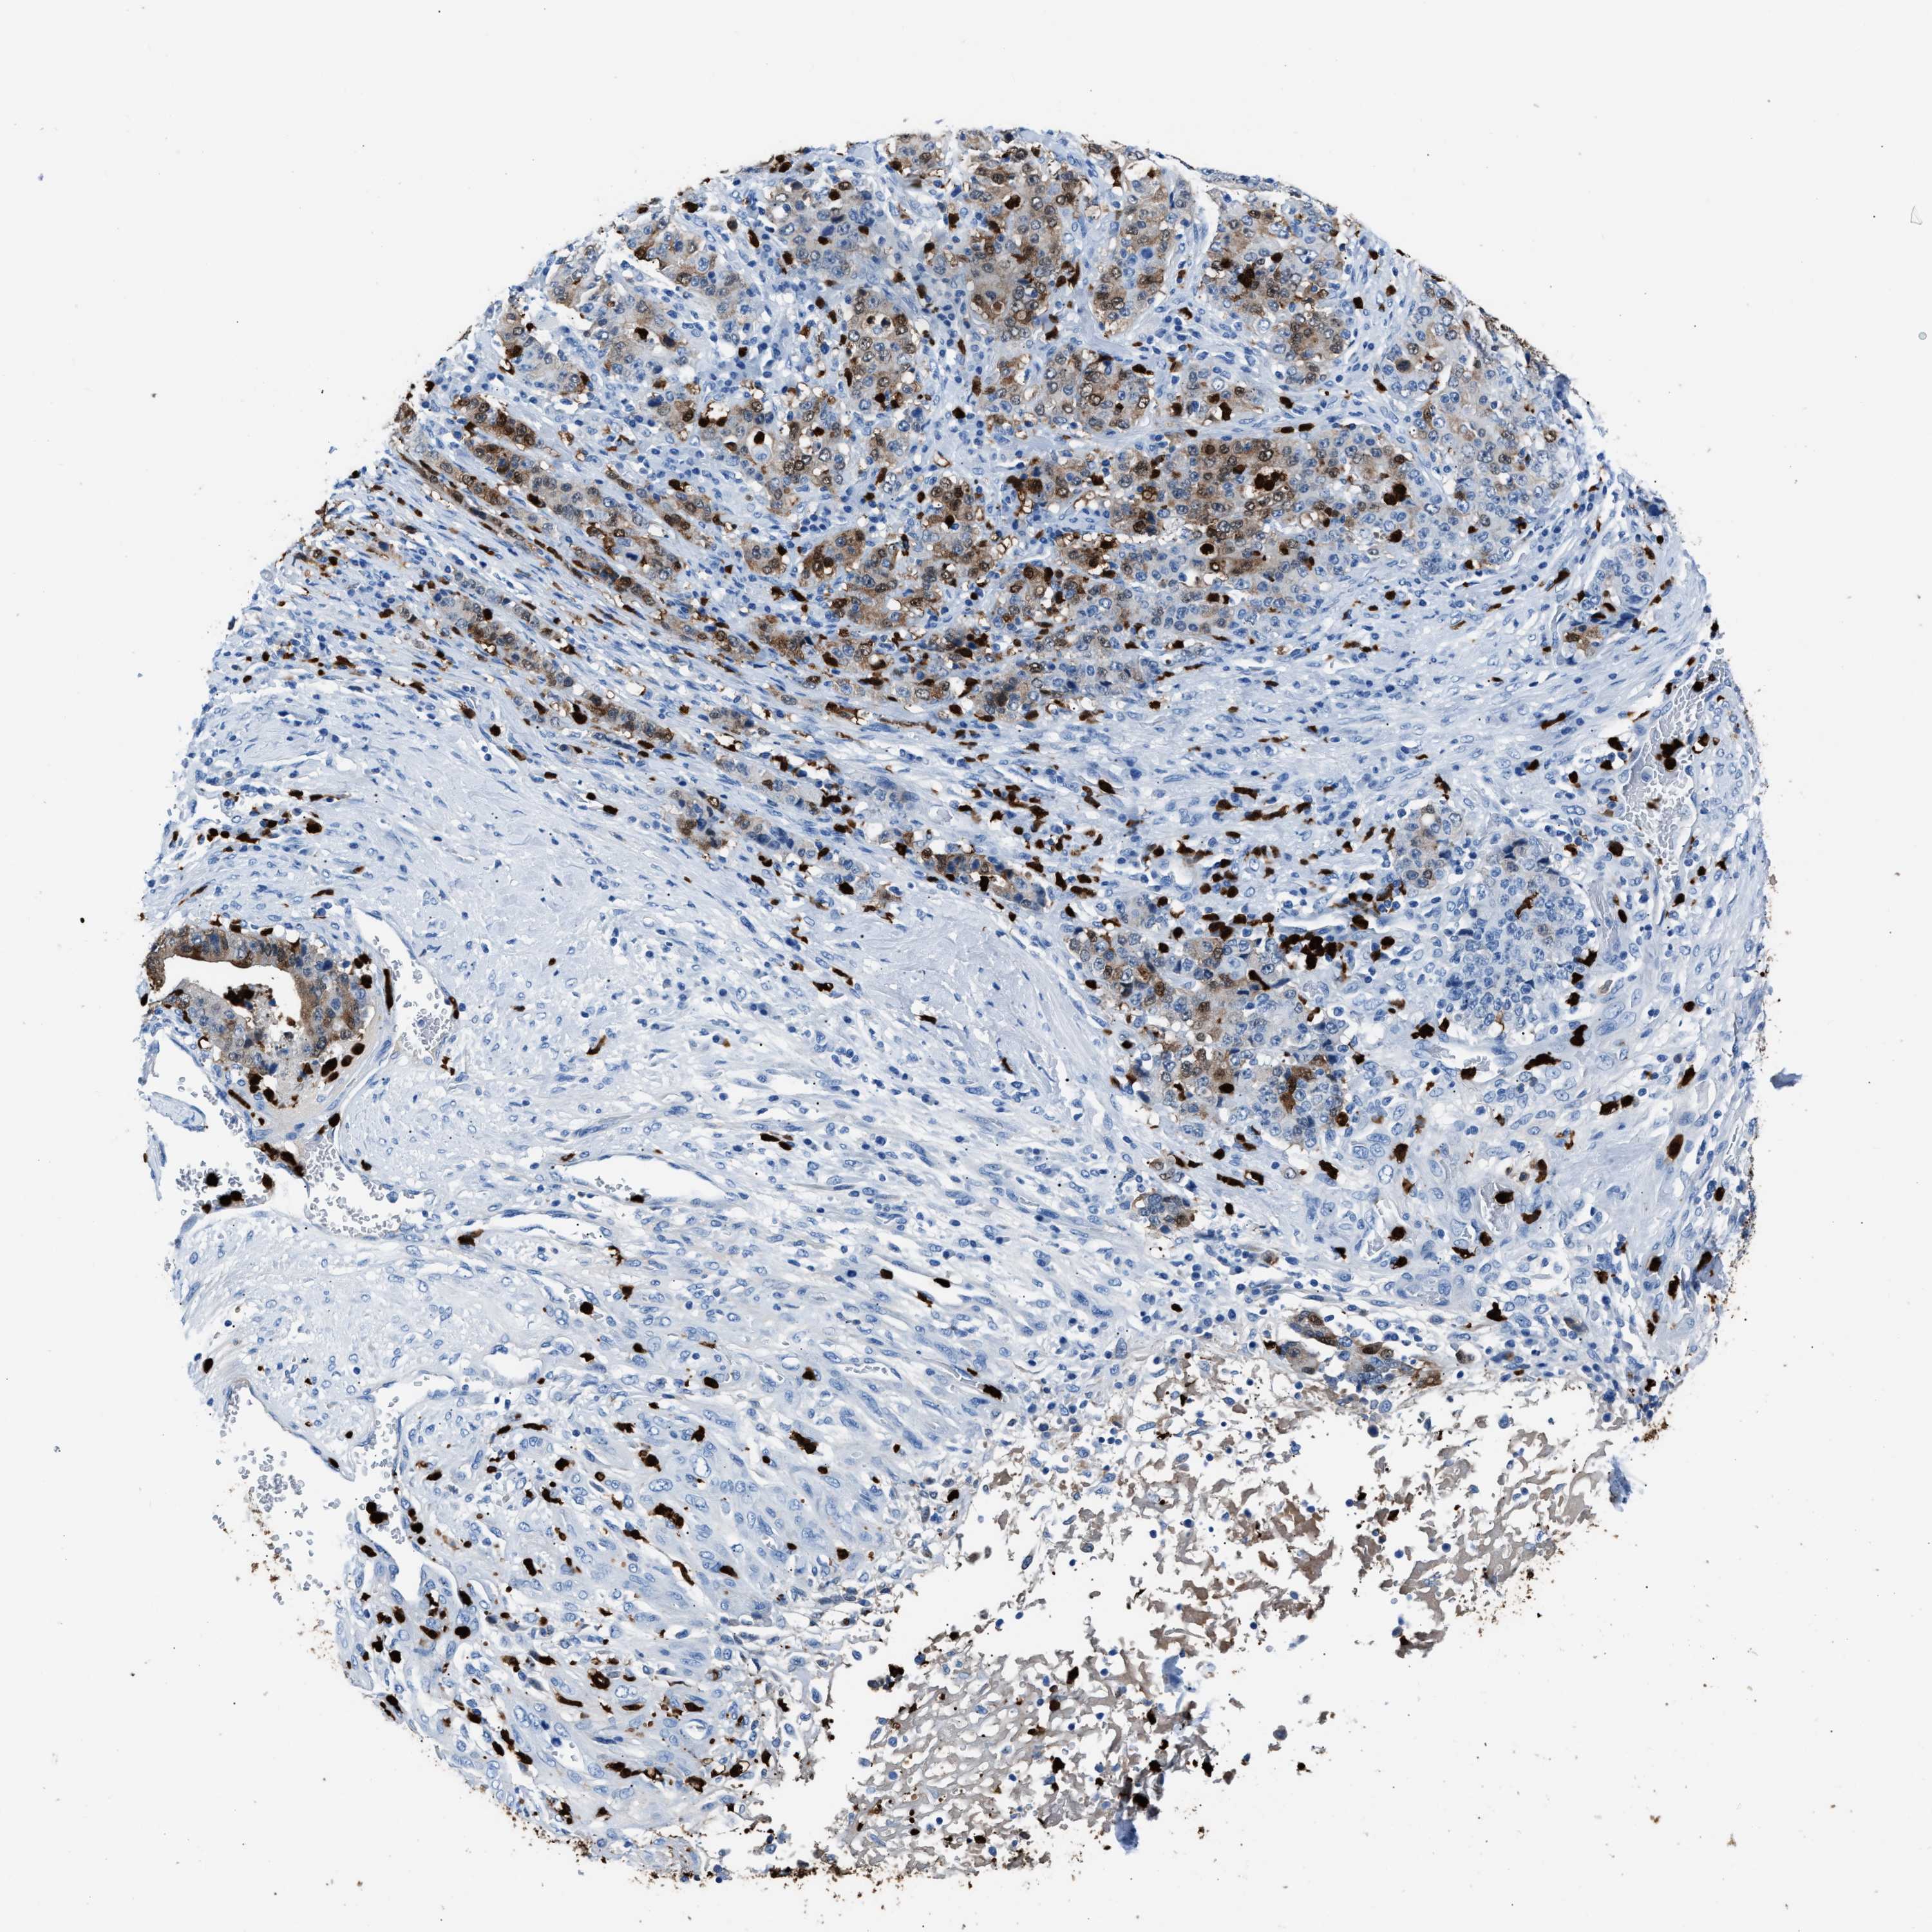

STOMACH CANCER - Protein expressioni

A mouse-over function shows sample information and annotation data. Click on an image to view it in a full screen mode. Samples can be filtered based on level of antibody staining by selecting one or several of the following categories: high, medium, low and not detected. The assay and annotation is described here.

Note that samples used for immunohistochemistry by the Human Protein Atlas do not correspond to samples in the TCGA dataset.

Antibody stainingi

Antibody staining in the annotated cell types in the current human tissue is reported as not detected, low, medium, or high, based on conventional immunohistochemistry profiling in selected tissues. This score is based on the combination of the staining intensity and fraction of stained cells.

Each image is clickable and will lead to virtual microscopy that enables deeper exploration of all samples and also displays staining intensity scores, fraction scores and subcellular localization as well as patient and tissue information for each sample.

Antibody HPA019502

Staining

High

Medium

Low

Not detected

Intensity

Strong

Moderate

Weak

Negative

Quantity

>75%

75%-25%

<25%

None

Location

Nuclear

Cytoplasmic/membranous

Cytoplasmic/membranous,nuclear

Adenocarcinoma, NOS